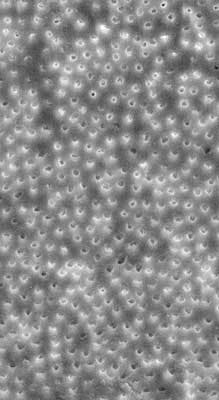

Sodium hypochlorite, which is often used during the root canal procedure as an irrigating disinfectant, can be very effective. However, it does have its limitations and may be insufficient in the removal of Enterococcus faecalis. (1) Research studies have documented sodium hypochlorite’s ability to dissolve pulp tissue and kill bacteria as well as weakening the canal walls. (2-3) We want the former and would like to eliminate the latter. We know that 17% ethylenediaminetetraacetic acid (EDTA) will remove the smear layer and open the dentinal tubules, allowing the more effective penetration of sodium hypochlorite at the further expense of weakening the canal walls. (3) In both cases, it is the high concentration of sodium hypochlorite and EDTA that potentiate each other to weaken the canal walls as an undesirable side effect of the chemical cleansing of the canal. Scanning electron microscope (SEM) images have shown the effective removal of the smear layer by 17% EDTA (figures 1-2). However, these SEM photographs also provided positive proof of dentin tubule erosion (figure 2).